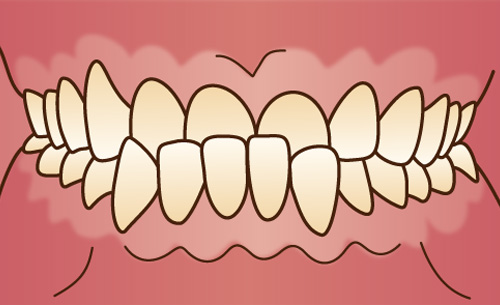

上下の歯が前に突き出ている状態で、顎の骨に問題がある場合と、歯だけが前に出ている場合とがあります。うまく噛むことができず、見た目も良くありません。唇を自然に閉じていられない場合もあります。